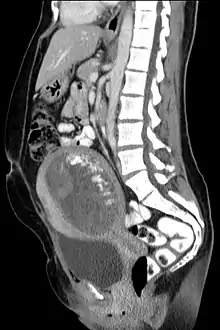

The diagnosis is strongly suggested by ultrasound (sonogram), but definitive diagnosis requires histopathological examination. On ultrasound, the mole resembles a bunch of grapes ("cluster of grapes" or "honeycombed uterus" or "snow-storm").[14] There is increased trophoblast proliferation and enlarging of the chorionic villi, and angiogenesis in the trophoblasts is impaired.[15]